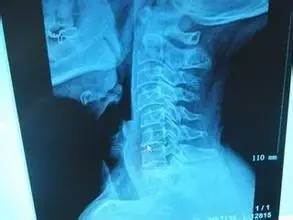

颈椎滑脱是指由于退变或头颈部应力作用导致病变颈椎发生移位。颈椎滑脱临床上较少见,发病率极低。